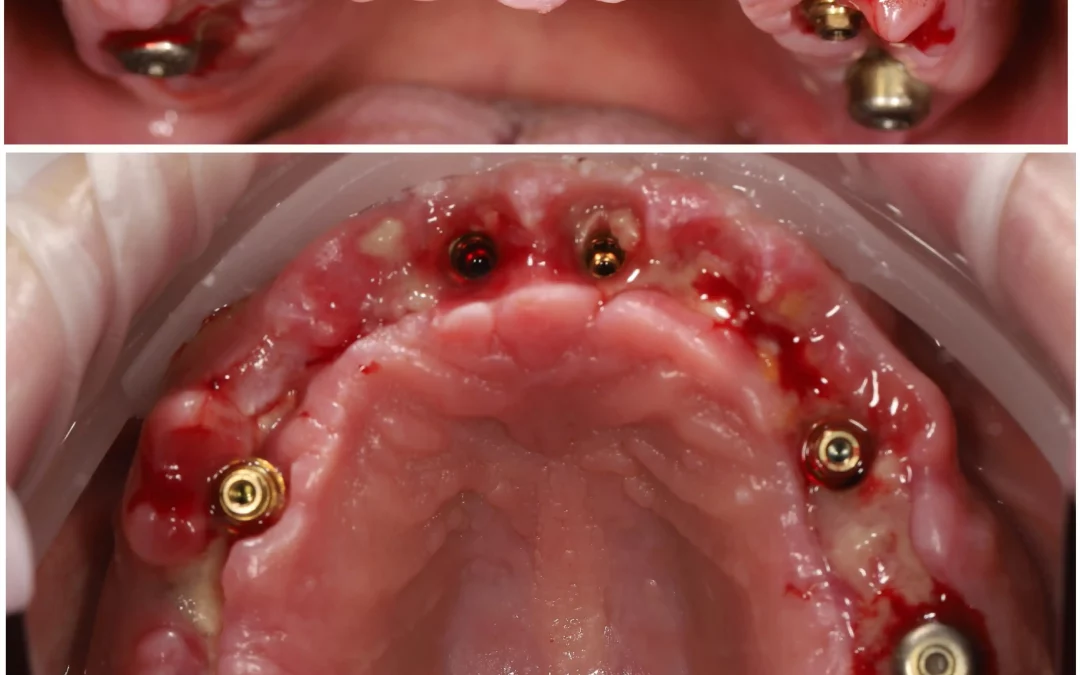

Ренат Ризванов | Клинический кейс RR-41

Тотальная реабилитация на верхней челюсти. Планирование и техническая часть: Игорь Лёвушкин Ортопед: Алексей Калашников В подобных случаях мы планируем накостные, либо гибридные шаблоны и преимущественно из...